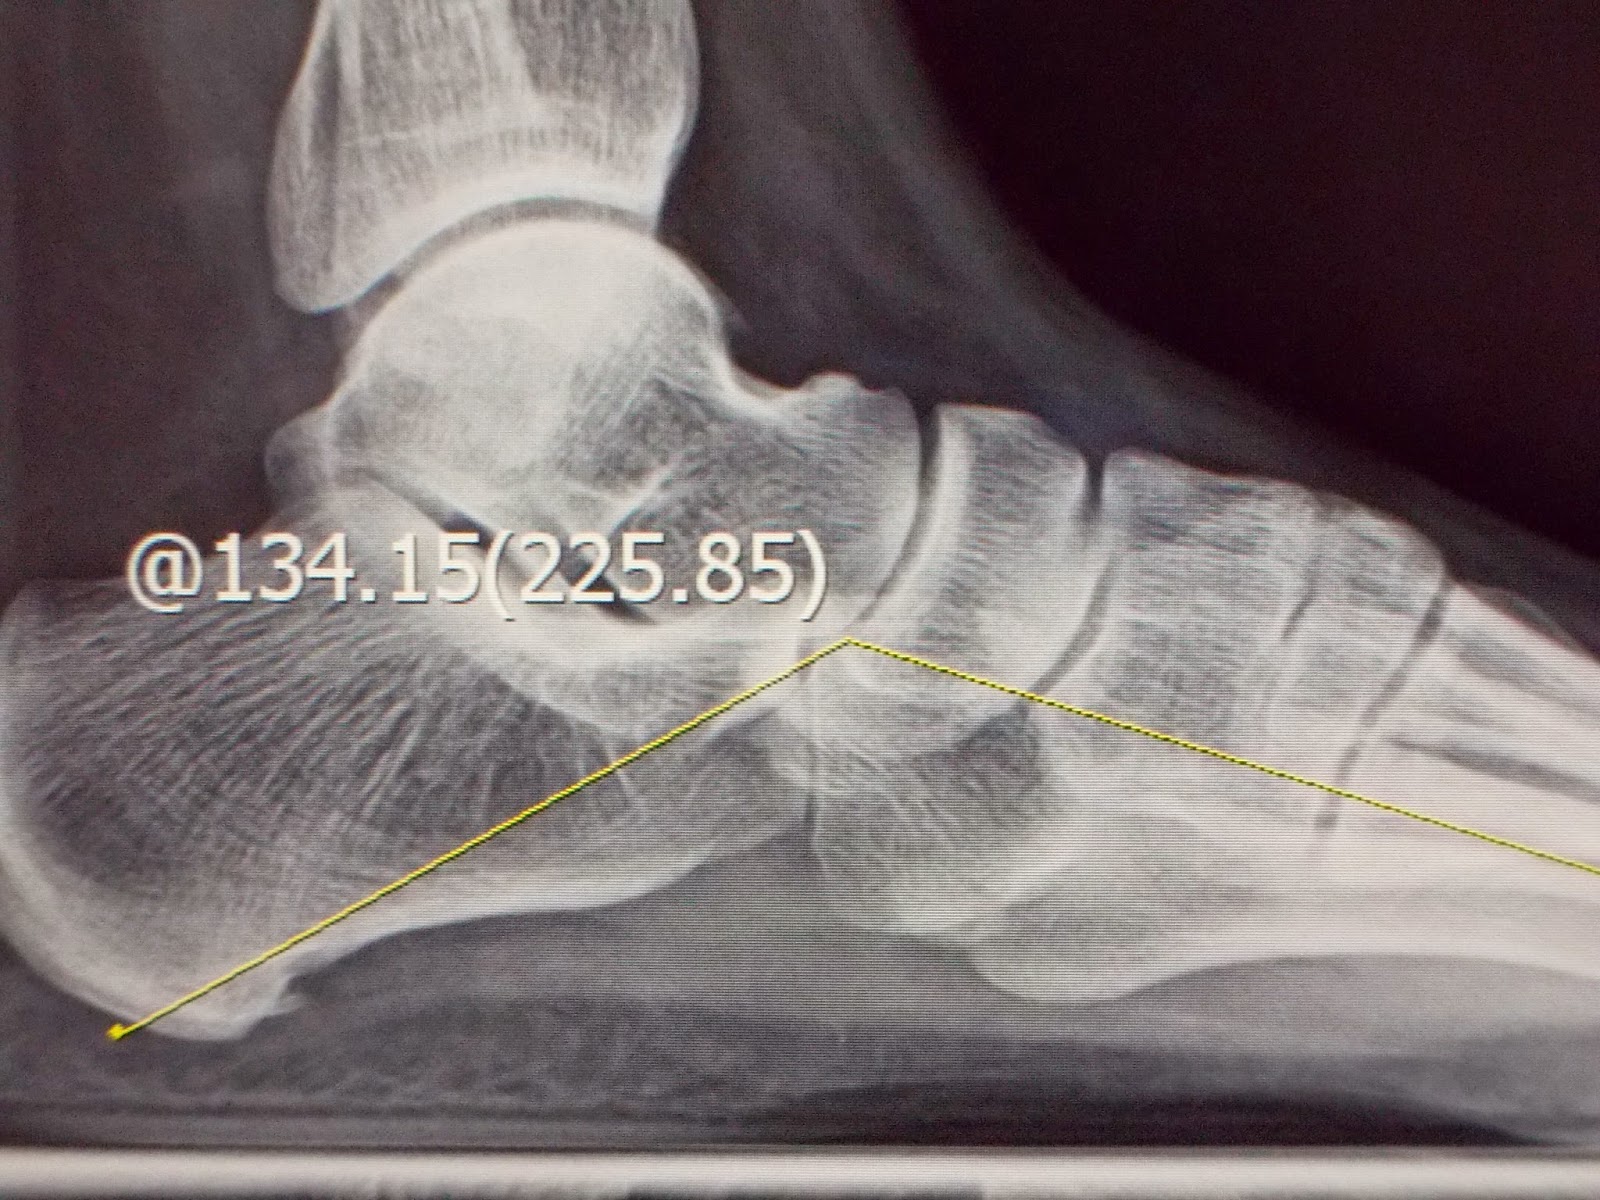

赤腳走路更可看出其特有的內傾(pronation)步態;以特定角度照的X光,更可看到某些負重骨骼間的相關角度有差異,或關節骨頭的一些變化(如圖),診斷並不困難。

(左圖:扁平足並足底筋膜炎. 右圖:扁平足 因距-舟狀骨關節退化及跗底肌腱炎 腳痛)